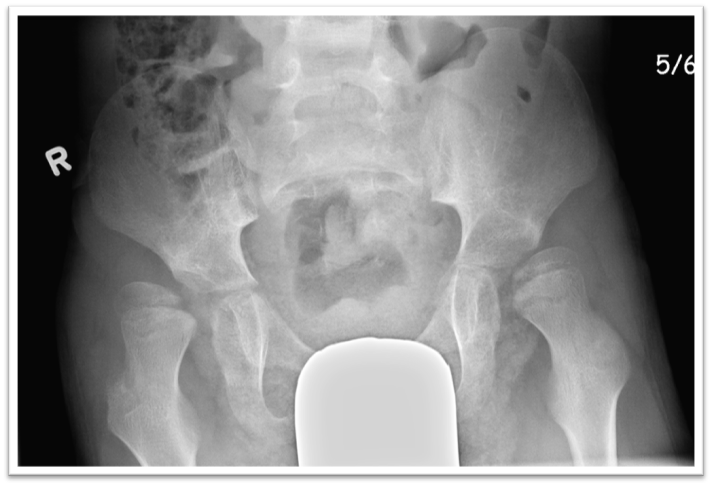

Hip displacement is common in children with cerebral palsy (CP) and CP can result in pain and difficulties with positioning, sitting, standing, and walking.

35% of children with CP are affected by hip displacement.

Hip surveillance is the process of monitoring and identifying the critical early indicators of hip displacement.

If hip displacement is not identified and acted upon early, complex and significant surgery can be required.

If caught early, there are interventions available, such as soft tissue and reconstructive hip surgeries, to prevent progressive displacement.

However, when hip displacement is identified at its late stages, the head of the femur may have already changed shape and lost cartilage.  When this happens, reconstructive surgery may no longer be possible and salvage surgery may be the only option.